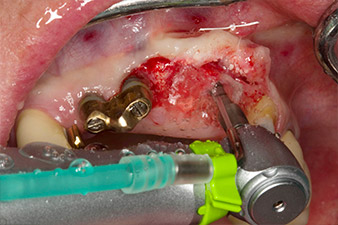

pilot drilling is performed with the new Implantmed and the WS-56 L contra-angle handpiece

Fig. 2: Two months later the pilot drilling is performed with the new Implantmed and the WS-56 L contra-angle handpiece (programme P1, ratio 1:1). The cooling is performed via the spray tube positioned on the left (for right-handed users).